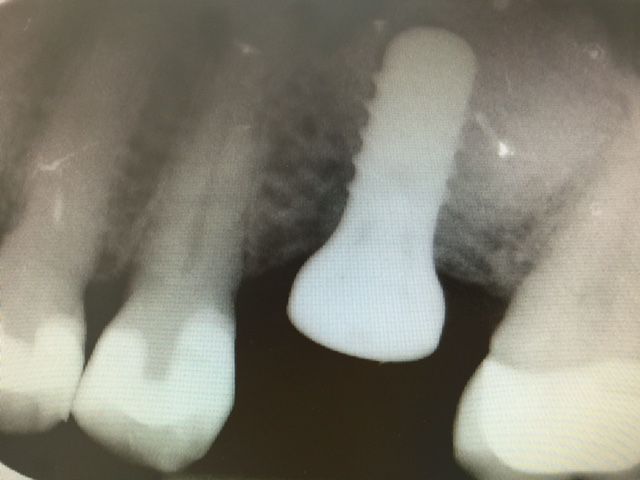

CAS N°1